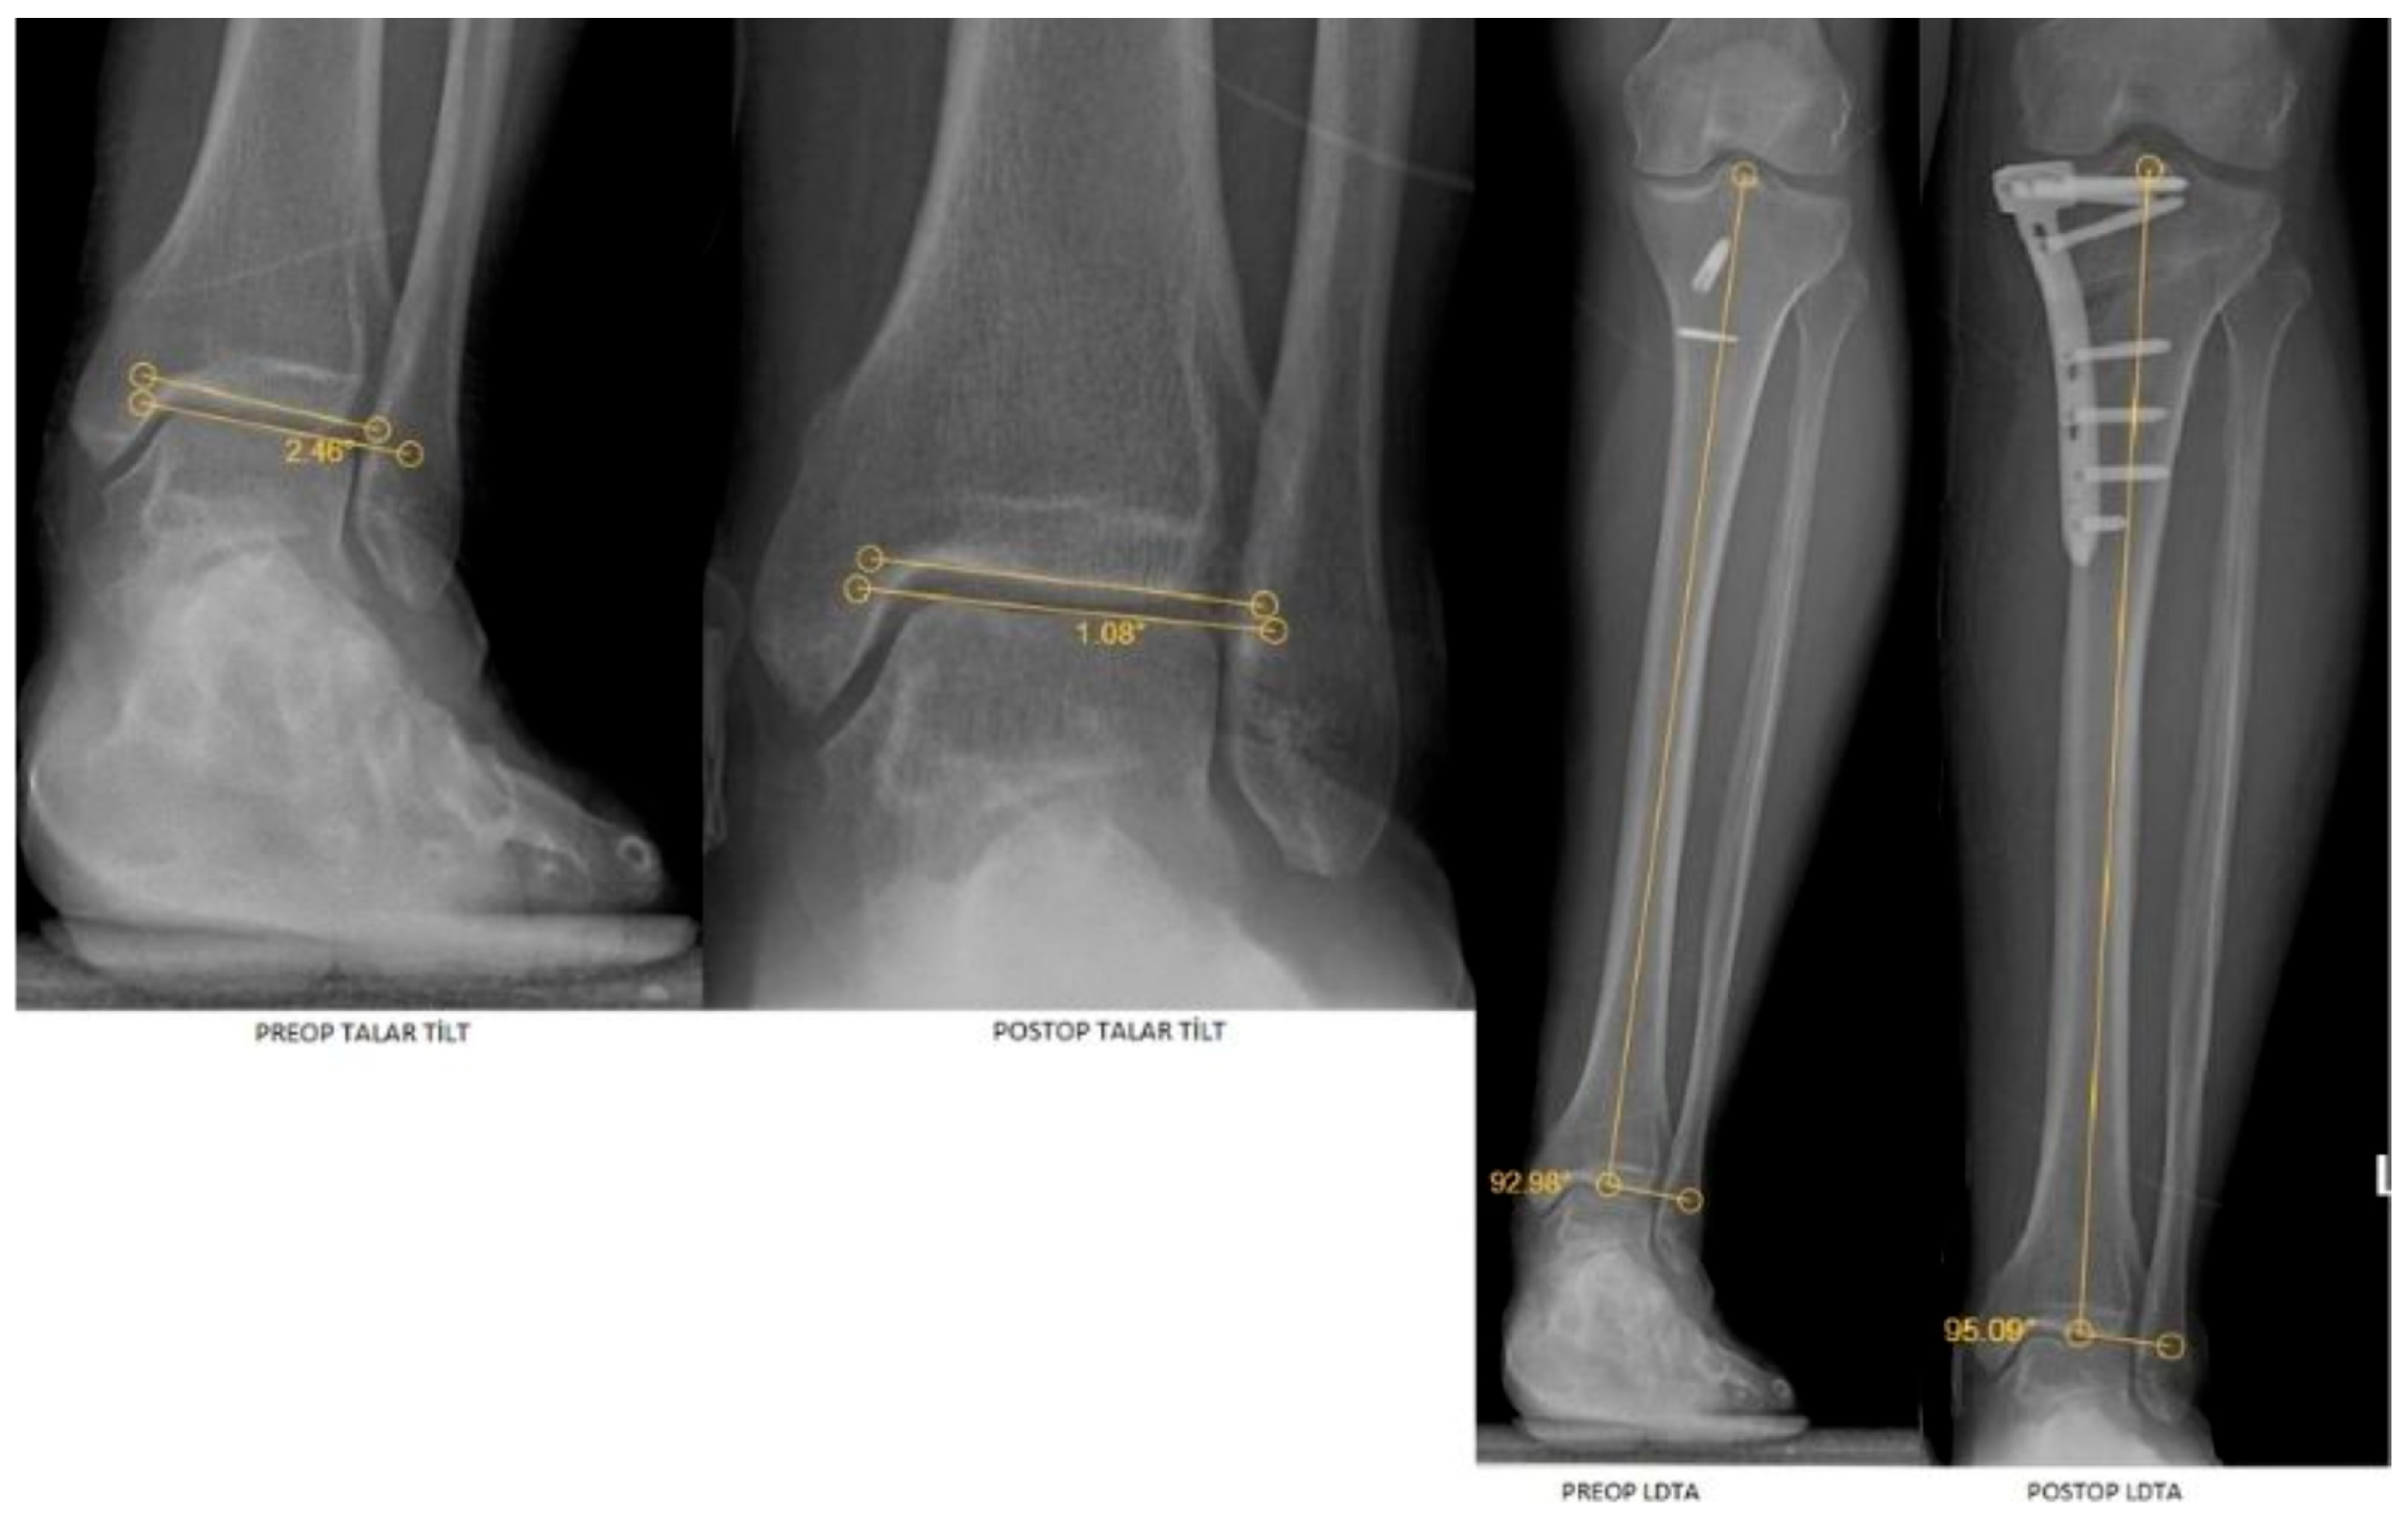

| LDTA | 87.25 (2.76) | 88.14 (2.24) | 0.018 a | 0.225 | 0.690 (0.577–0.776) |

| MPTA | 83 (4.53) | 87.40 (2.71) | <0.001 a | 0.838 | 0.441 (0.277–0.579) |

| HKA | 171.44 ± 3.35 | 177.11 ± 2.32 | <0.001 b | −1.804 | 0.404 (0.235–0.549) |

| JLCA | 3.18 (1.94) | 1.95 (1.12) | <0.001 a | 0.798 | 0.692 (0.580–0.778) |

| Talar tilt | 0.85 (0.51) | 0.70 (0.52) | <0.001 a | 0.752 | 0.863 (0.806–0.904) |